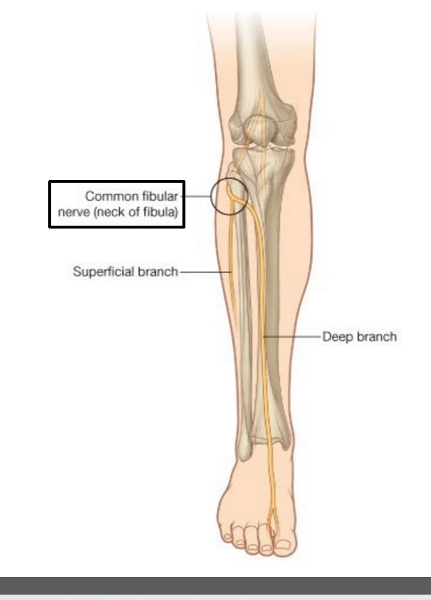

Describe the pathway of the common fibular nerve

wraps around the neck of the fibula

bifurcates into deep and superficial fibular nerves

The nerve that wraps around the neck of the fibula is the _______

common fibular

O C D of common fibular nerve

O sciatic nerve

C forms as sciatic nerve bifurcates at apex of popliteal fossa. follows medial border of biceps femoris with its tendon. passes over posterior aspect of head of fibula then winds around neck of fibula deep into fibularis longus where it divides into deep and superficial fibular nerves

D knee joint via articular branch and lateral aspect of posterior leg via sural cutaneous nerve

(common fibular branch of sciatic nerve innervates short head of biceps femoris)